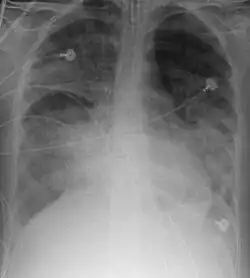

Insuficiência respiratória

O termo insuficiência respiratória, em medicina, é usado para descrever a troca inadequada de gases pelo sistema respiratório, resultando numa incapacidade de manter os níveis de oxigênio e dióxido de carbono arteriais dentro dos níveis normais. A baixa oxigenação é denominada como hipoxemia e um aumento dos níveis sanguíneos de dióxido de carbono denomina-se hipercapnia.